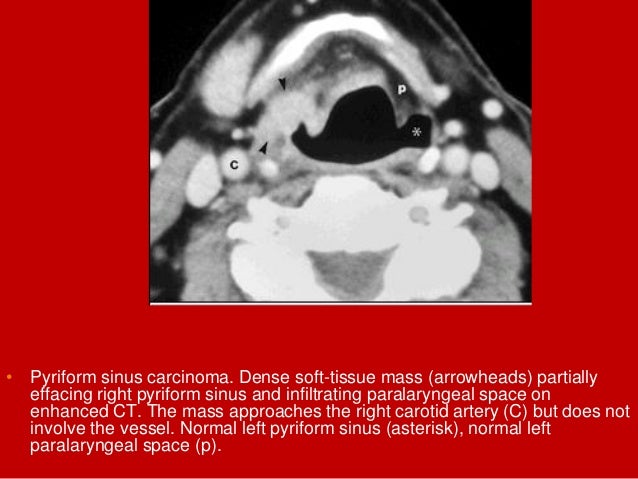

66. 66. • Pyriform sinus carcinoma. Dense soft-tissue mass (arrowheads) partially effacing right pyriform sinus and infiltrating paralaryngeal space on enhanced CT. The mass approaches the right carotid artery (C) but does not involve the vessel. Normal left pyriform sinus (asterisk), normal left paralaryngeal space (p).